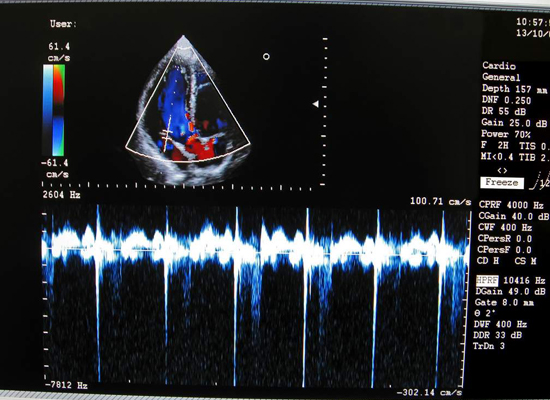

• Doppler y vascular periférico

La elastografia tal cual su nombre lo indica es una técnica ultrasonigrafica en codificación de colores los cuales van a variar de acuerdo a la elasticidad específica de los tejidos. Una característica de posibles lesiones malignas es la pérdida de esta elasticidad de tal forma el doctor al realizar el estudio al notar esta pérdida de elasticidad ayuda significativamente a su diagnóstico.